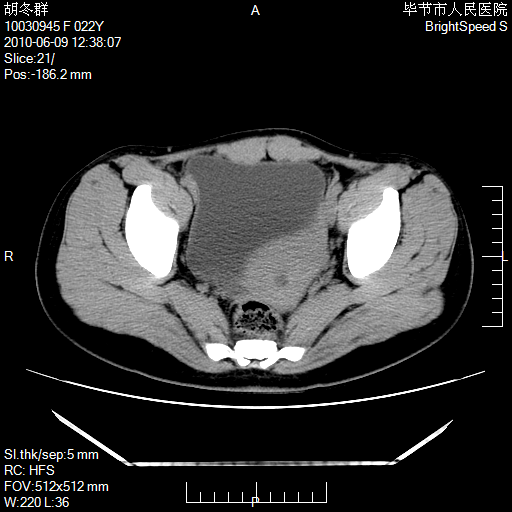

患者23岁,发现腹部包块3月。

左侧卵巢囊腺瘤或囊腺癌

盆腔内囊性占位性病变;考虑左侧卵巢囊腺瘤。

有分隔、壁薄,支持考虑左侧卵巢囊腺瘤。

左侧卵巢浆液性囊腺瘤。

支持考虑左侧卵巢囊腺瘤;宫腔积液。

有分隔、壁薄,支持考虑左侧卵巢囊腺瘤。排尿后,膀胱缩小,由于重力作用,肿块下移就到了膀胱位置,很好理解。